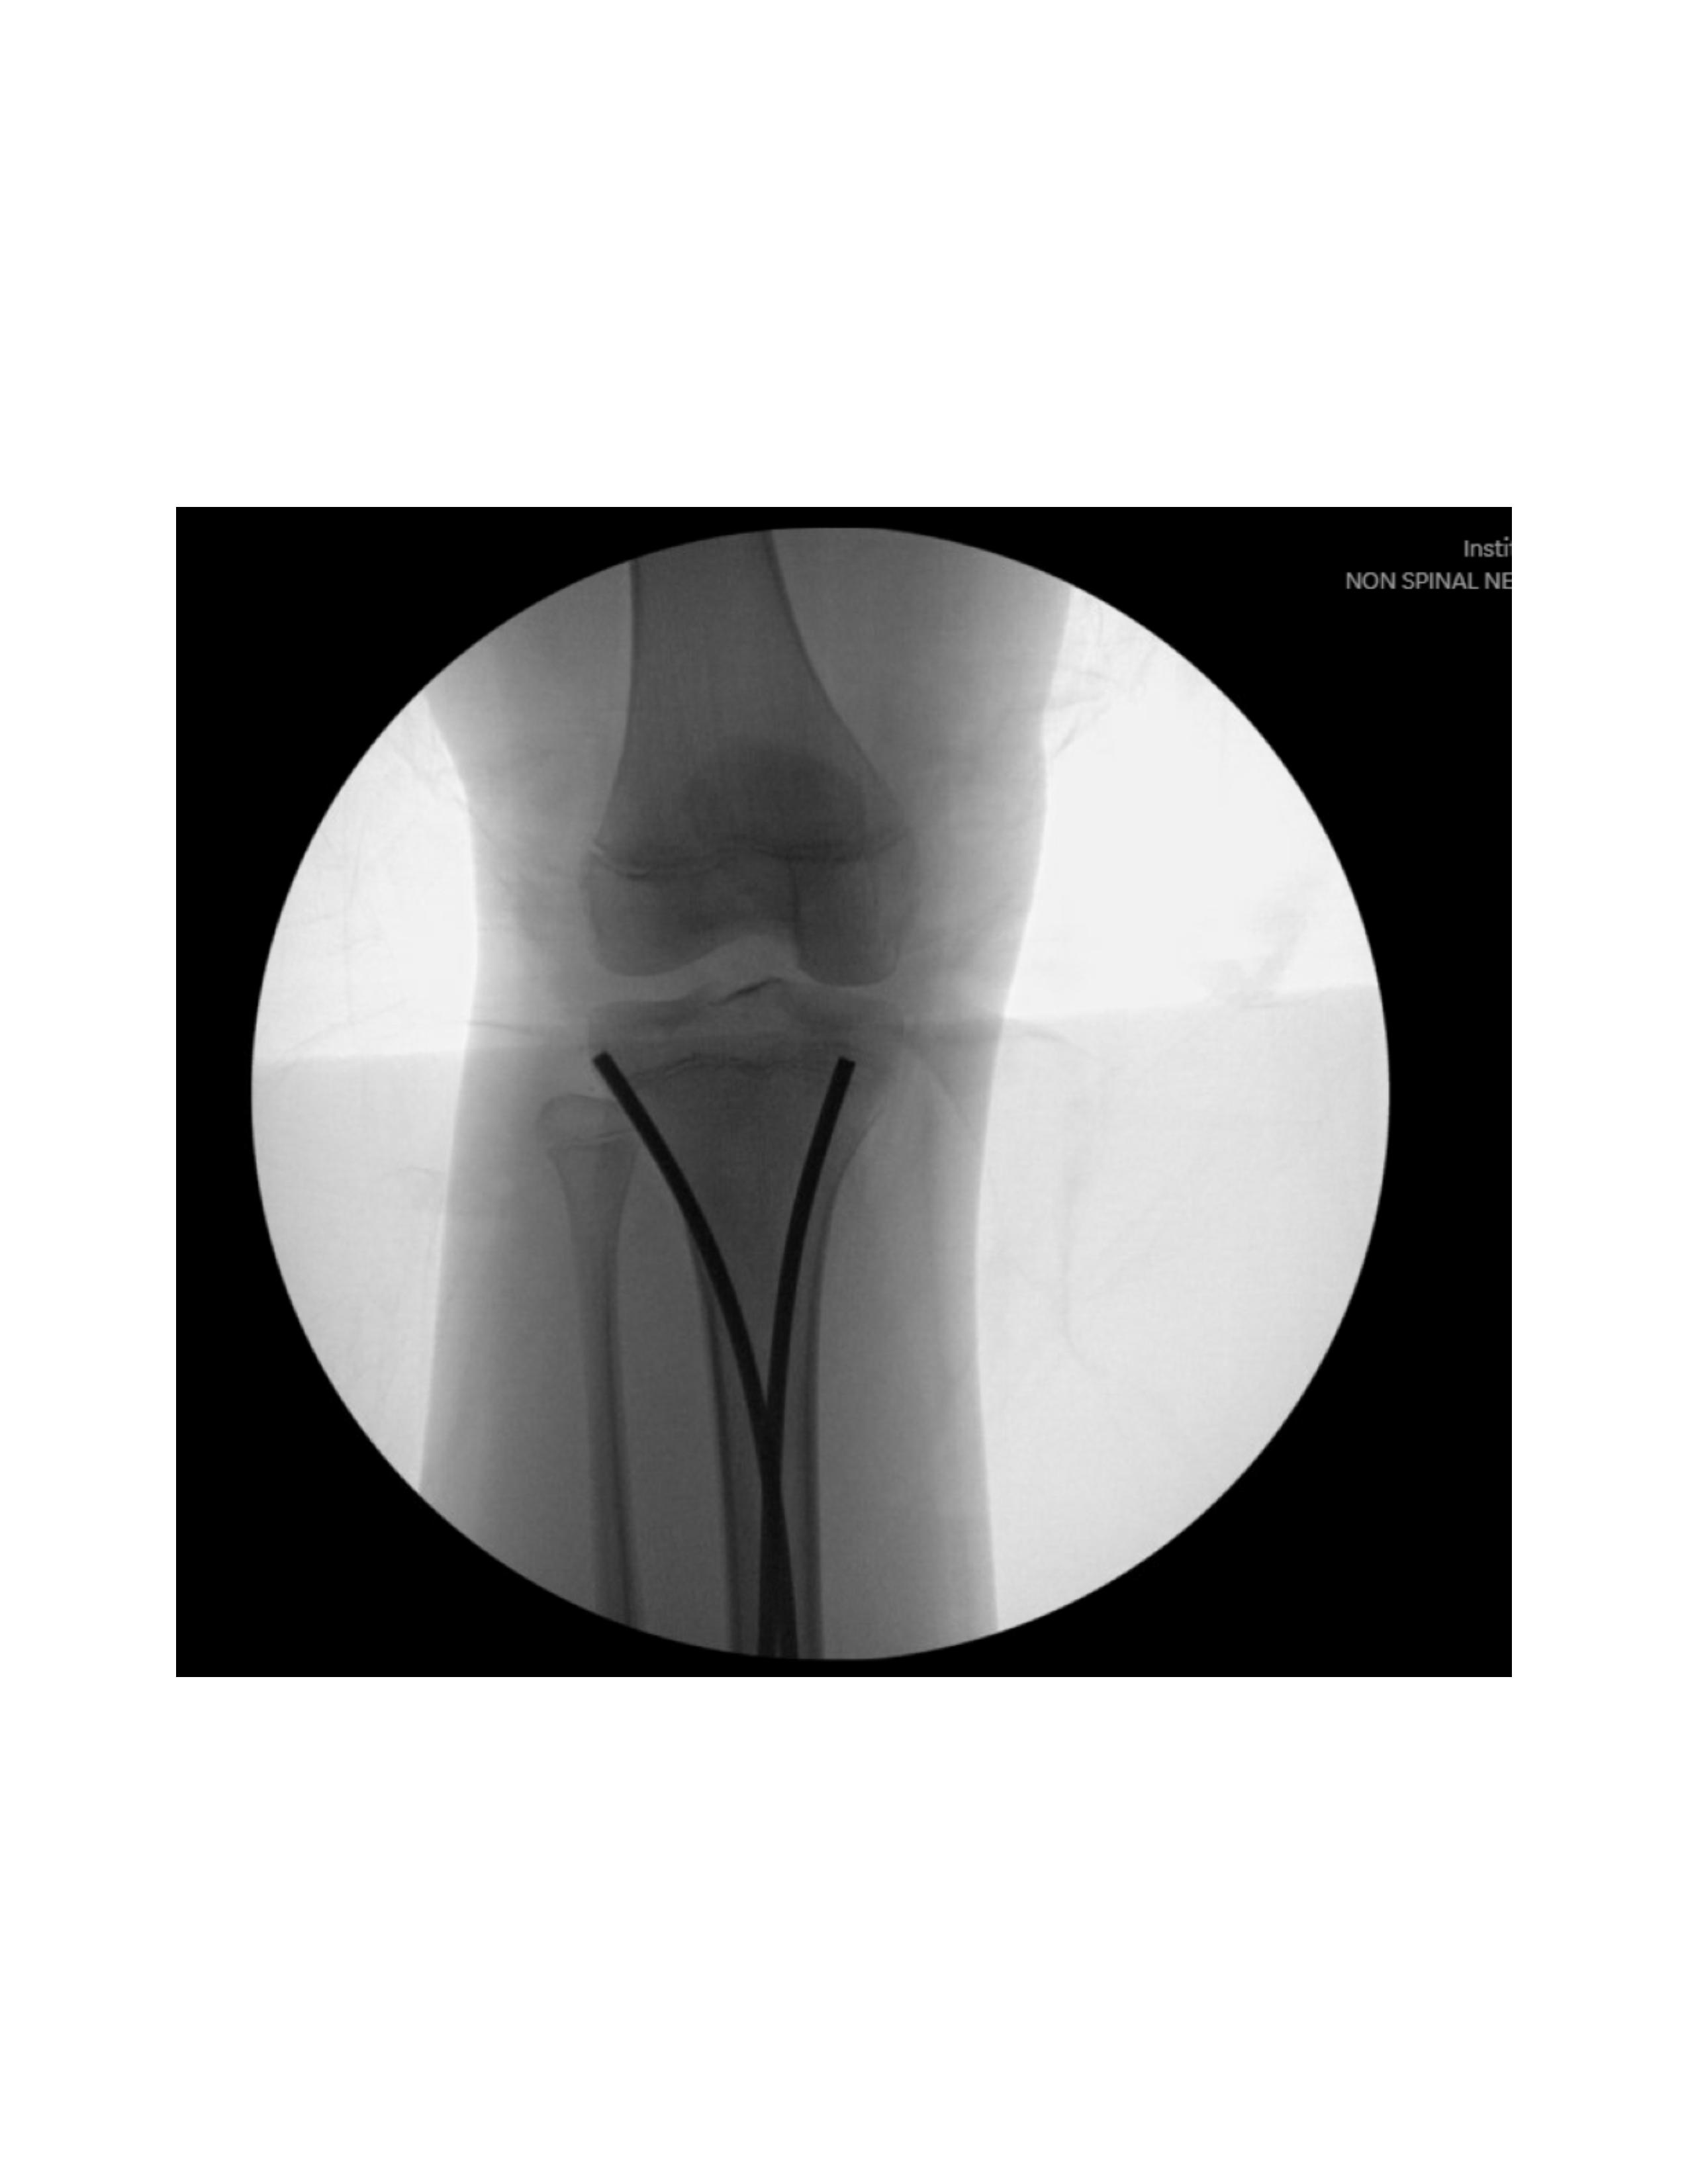

Next, lateral entry point is made with a 2-3 cm longitudinal incision over the anterior compartment musculature between the tibial crest and the fibula head, 10-30 mm distal to the proximal physis. After blunt dissection, fascia splitting anteriorly, and lifting the anterior 6 compartment musculature off the tibia, a drill is utilized under fluoroscopy to enter the cortex anterior to the lateral border of the interosseous membrane attachment site. The modified nail is inserted using an inserter/T-handle with the curved tip perpendicular to the medial cortex (Figure 3). Oscillatory motions facilitate entry into the medullary canal until contact is made with the far cortex. The nail is then advanced by a mallet proximal to the fracture site before addressing the medial nail.

A similar incision is made over the medial tibia, 10-30 mm distal to the proximal physis. After blunt dissection to the bone posterior to the midsection of the medial metaphysis, a drill is utilized under fluoroscopy to create an entry hole between the pes anserine tendons and the medial collateral ligament insertion site. The modified nail is inserted similarly (Figure 4).